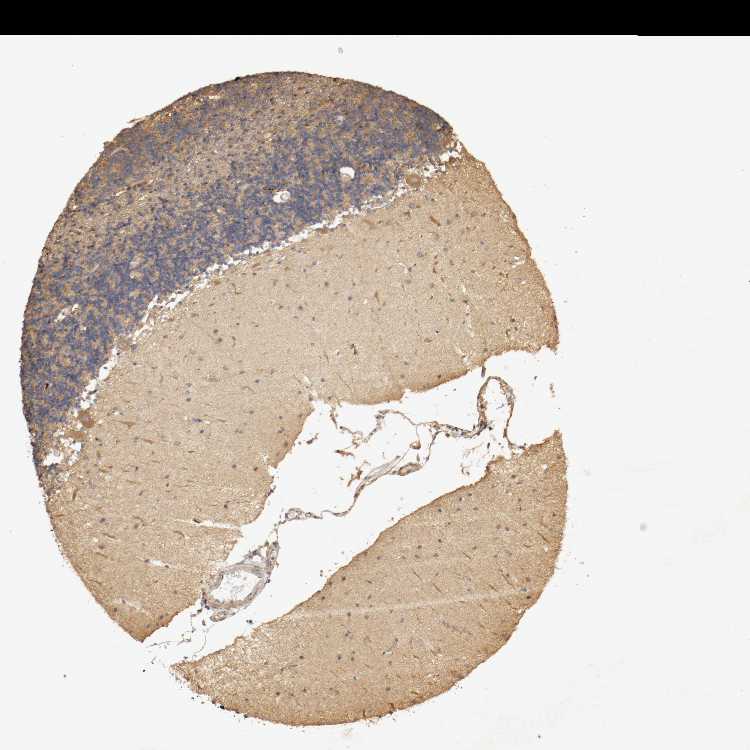

CEREBELLUM - Expression summary

CEREBELLUM - Antibody stainingi

Antibody staining in the annotated cell types in the current human tissue is reported as not detected, low, medium, or high, based on conventional immunohistochemistry profiling in selected tissues. This score is based on the combination of the staining intensity and fraction of stained cells.

Each image is clickable and will lead to virtual microscopy that enables deeper exploration of all samples and also displays staining intensity scores, fraction scores and subcellular localization as well as patient and tissue information for each sample.

Antibody HPA004811Antibody HPA017066

Purkinje cells HighHigh

Cells in granular layer MediumMedium

Cells in molecular layer MediumMedium